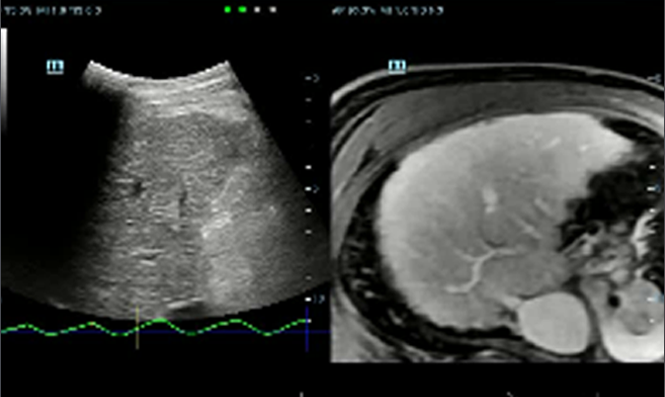

Imagerie ultrasonore par ûˋmission d'ondes planes alimentûˋe par la technologie ZST+, le HiFR CEUS permet une capture CEUS ultra rapide pour la visualisation de la structure vasculaire et des caractûˋristiques de perfusion en phase artûˋrielle, fonctionnant comme un outil complûˋmentaire de l'UWN+

Cas d'utilisation du HiFR CEUS?: HNF du foie

*Il n'est pas recommandûˋ d'appliquer le HiFR CEUS dans la phase de retardement ou dans une rûˋgion û 10?cm de profondeur

?valuation intelligente de la stûˋatose hûˋpatique par le calcul automatique de la luminositûˋ hûˋpatique avec le cortex rûˋnal en mode?B.

Imagerie de fusion ûˋchographique en 3D

Imagerie de fusion ûˋchographique en 3D

Compensation respiratoire

Compensation respiratoire